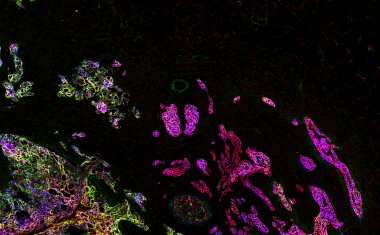

Lungenkrebs ist sehr unterschiedlich, was die Behandlung erschwert. Forscher des BIH an der Charité haben ein Verfahren entwickelt, bei dem Mini-Tumoren aus Patientenproben gezüchtet und verschiedene Therapien getestet werden.